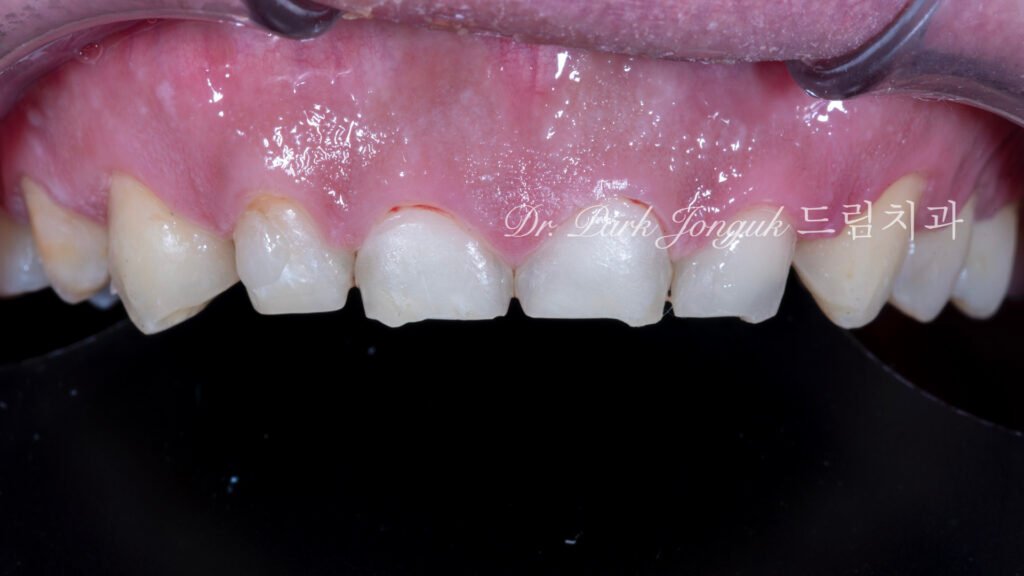

2. 임상 상태 분석 및 치료 계획 (사진 1)

2.1 교정 완료 후의 한계점

[사진 1 참조] 환자분은 부정교합을 해결하기 위해 교정 치료를 먼저 진행하셨습니다. 하지만 교정은 치아의 ‘위치’를 바로잡을 뿐, 위산에 의해 변형된 치아의 ‘형태’와 ‘두께’까지 회복시켜 주지는 못합니다. 치아 표면은 이미 얇아질 대로 얇아져 있었으며, 법랑질 소실로 인해 상아질 노출의 위험이 있는 상태였습니다.

2.2 보존과 전문의의 판단

이 상태에서 기존의 라미네이트 방식(삭제형)을 선택하는 것은 치아의 수명을 급격히 단축시키는 위험한 선택입니다. 이에 저는 남은 치질을 100% 보존하면서 결손된 부위만 정교하게 덧붙이는 **무삭제 라미네이트(Non-Prep Veneer)**를 최종 솔루션으로 결정했습니다.